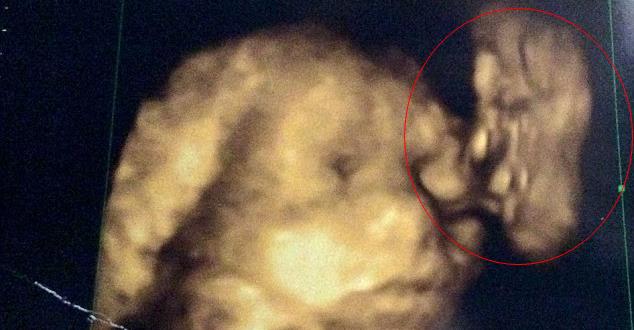

英国伦敦一名准妈妈日前到医院进行4D超音波,意外发现超音波照片,可清晰看见一张脸在亲吻胎儿的模样,而那张脸彷佛是她已逝的爷爷。

回家仔细看照片时,惊见胎儿旁边有一个疑似人脸的影像,而这个人脸影像像极了霍斯比的爷爷,还噘起嘴唇,像在亲吻婴儿的脸颊。

霍斯比完全惊呆了,她表示,「爷爷在2007年就过世了,这个影像真的太像他了,他的轮廓比我女儿还清楚可见,相信这是爷爷的祝福,也相信爷爷会永远守护着她们」。